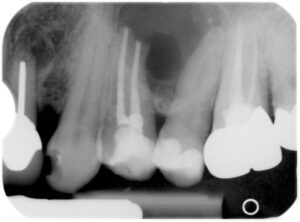

Wie wurde das Problem gelöst?

Im Rahmen einer Wurzelspitzenresektion hat man sich durch einen kleinen Schleimhautschnitt ein Zugang zur Zyste und der Wurzelspitze geschaffen. Die Zyste wurde entfernt, die Wurzelspitze gekappt und die Wurzelfüllung erneuert. Das erste Röntgenbild zeigt den Zustand direkt nach dem Eingriff. Ein Jahr später (zweites Bild) ist der durch das Zystenwachstum entstandene Knochendefekt wieder vollständig ausgeheilt. Darüber hinaus sind die Wurzelspitzen des ursächlichen Zahnes und des Zahnes rechts davon wieder annähernd parallel.